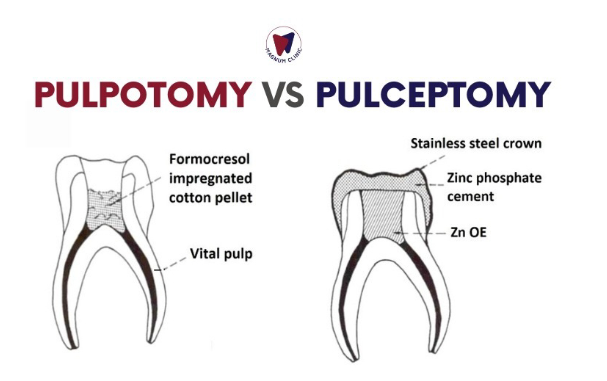

PULPECTOMY